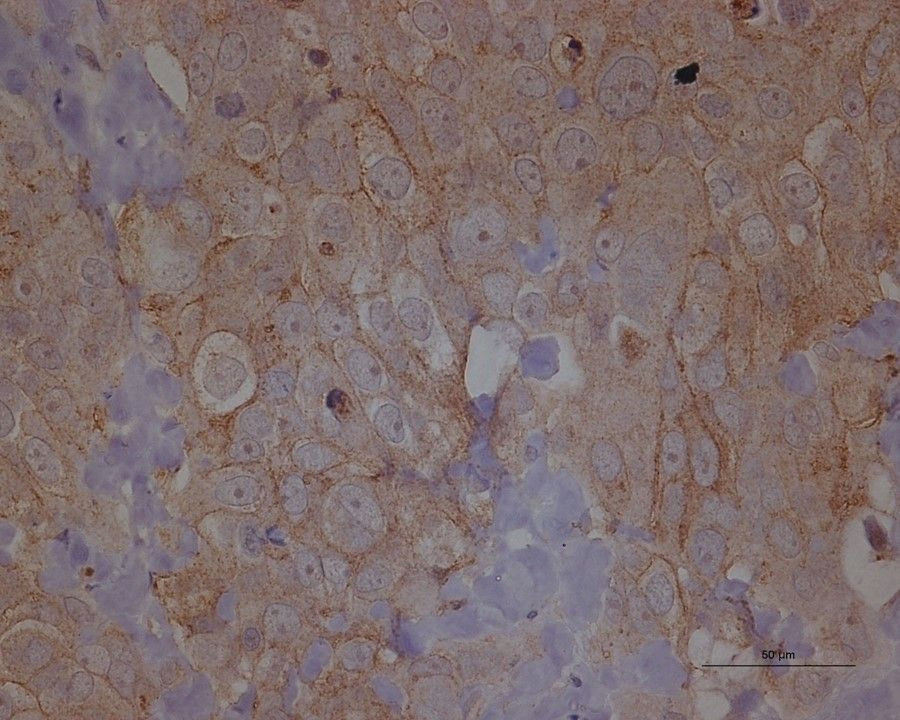

En el estudio, el equipo buscó un tipo específico de metabolón, llamado purinosoma, que se cree que lleva a cabo la biosíntesis de purina de novo, el proceso mediante el cual las nuevas purinas - bloques de construcción de ADN y ARN - son sintetizados. Los investigadores estudiaron estos purinosomas dentro de las células HeLa, una línea celular de cáncer de cuello uterino comúnmente utilizada en la investigación científica.

Los investigadores identificaron los purinosomas, que tenían menos de un micrómetro de diámetro, utilizando un novedoso sistema de imágenes desarrollado por Nicholas Winograd, profesor de química de la Universidad Evan Pugh y sus colegas.

"La técnica utiliza la espectrometría de masas de iones secundarios del haz de iones del grupo de gases (GCIB-SIMS) para detectar biomoléculas intactas con alta sensibilidad y permitir la obtención de imágenes químicas in situ en células individuales --explica Hua Tian, profesor asistente de investigación, Departamento de Química e Instituto de Investigación de Materiales--. Esto fue vital para el estudio ya que estamos tratando con una concentración muy baja de moléculas en células cancerosas individuales".